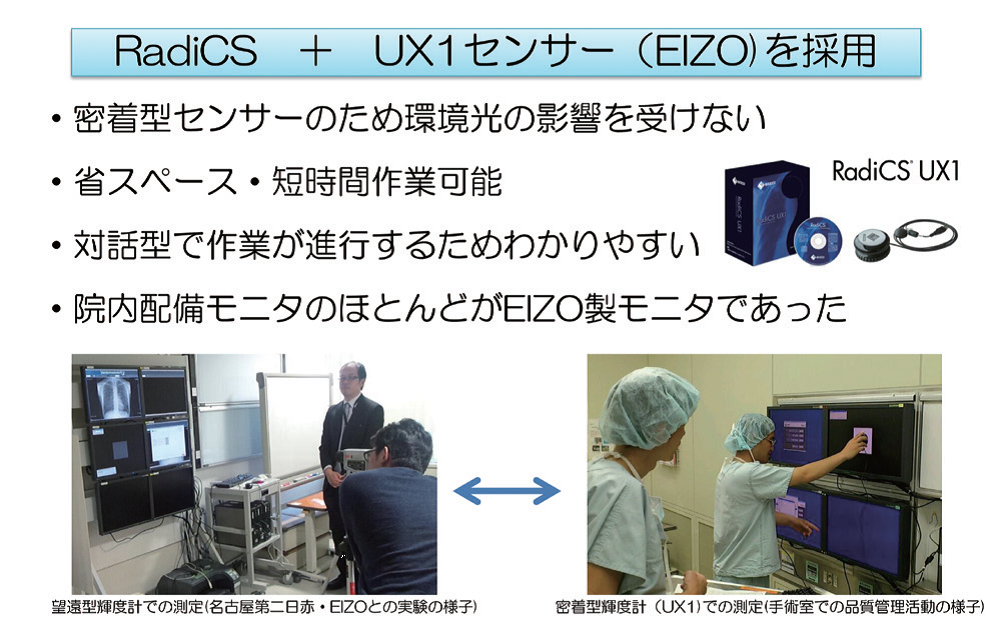

京都第二赤十字病院でのモニタ品質管理の取り組み

実施には部門全体で取り組み、過度な負担のない参加型としている(図2)。QC班は6名で、1、2カ月に一度、業務終了後2時間を目処に行い、1年かけて院内全台に実施する体制を構築した。